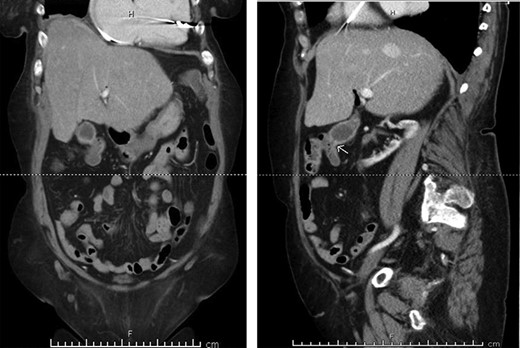

A 70-year-old female with congestive heart failure, atrial fibrillation, and end-stage renal disease presented to the general surgery clinic with a radiographic finding of a CCF. During workup for upper gastrointestinal bleeding, a computed tomography (CT) enterography incidentally demonstrated a fistulous connection between her gallbladder and the proximal transverse colon (Fig. 1). In the clinic, she reported right upper back pain that was unrelated to meals. She had no abdominal tenderness and her liver function tests were within normal limits.

Preoperative CT enterography demonstrating a CCF; (a) coronal view and (b) sagittal view, the white arrow indicates the location of the fistula.